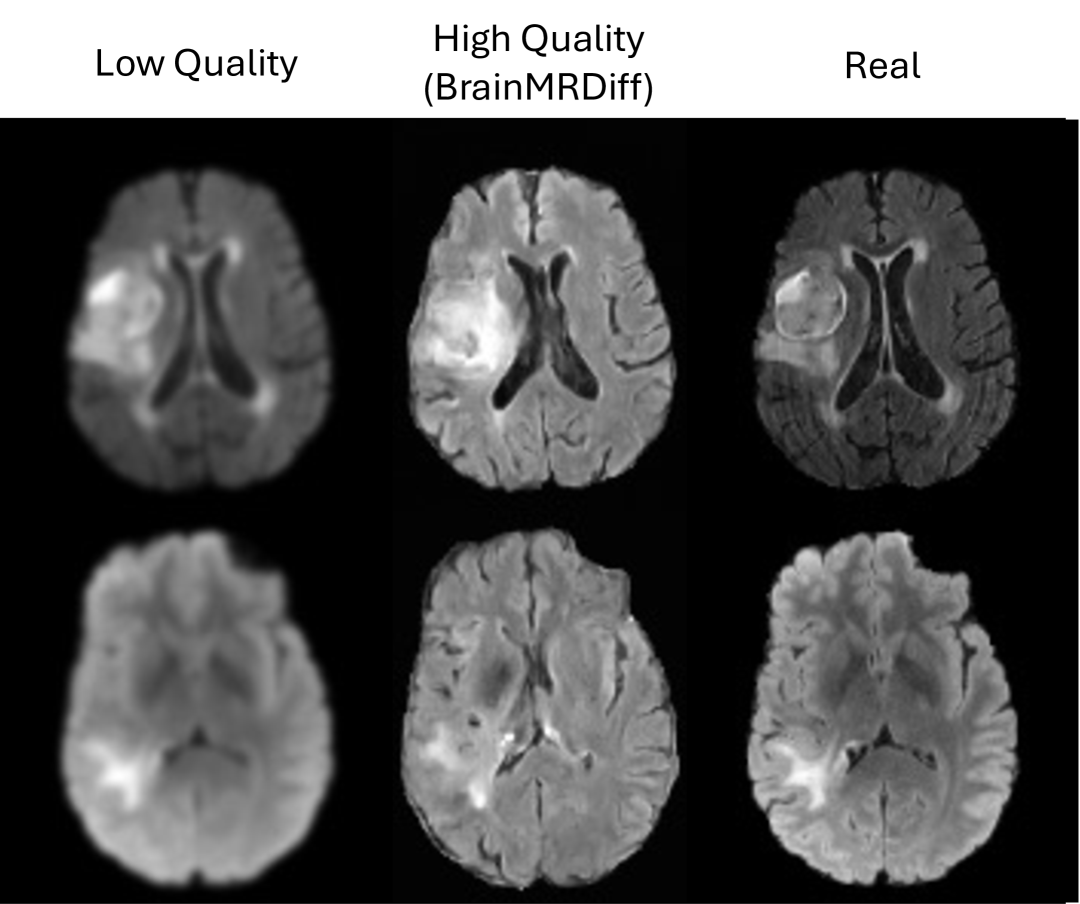

Beyond the IQA and segmentation experiments, we also evaluate our method on three clinically relevant tasks: High-quality image generation, MGMT status prediction and survival analysis.

High quality image generation. We artificially add gaussian noise to the images to create low quality images. From these low quality images, we obtain the anatomical structures and use them as control to BrainMRDiff. In Fig. 8, we observe that BrainMRDiff generates a high-quality FLAIR sequence that closely resembles the real FLAIR sequence. Tab. 6 presents the PSNR scores across varying noise levels. Notably, the generated image quality remains consistent regardless of noise intensity.